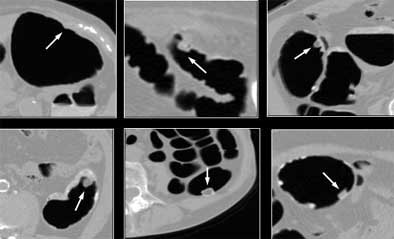

![]() |

| The presence of untagged or partially tagged stool in images above led to false-positive results with CAD. |

"There were some cases that were partially covered by stool, which were unfortunately missed by CAD," he said. In fact, untagged or partially tagged stool was the principle cause of false-positives (40%), followed closely by haustral folds (39.3%), nonspecific findings (4.1%), stomach or small bowel (4.1%), ileocecal valve (4.1%), extrinsic compression (0.7%), rectal tube (0.1%), and other findings (6.2%) the CAD scheme took as polyps, and which the radiologist would presumably eliminate upon inspection of the CAD results, according to Yoshida.